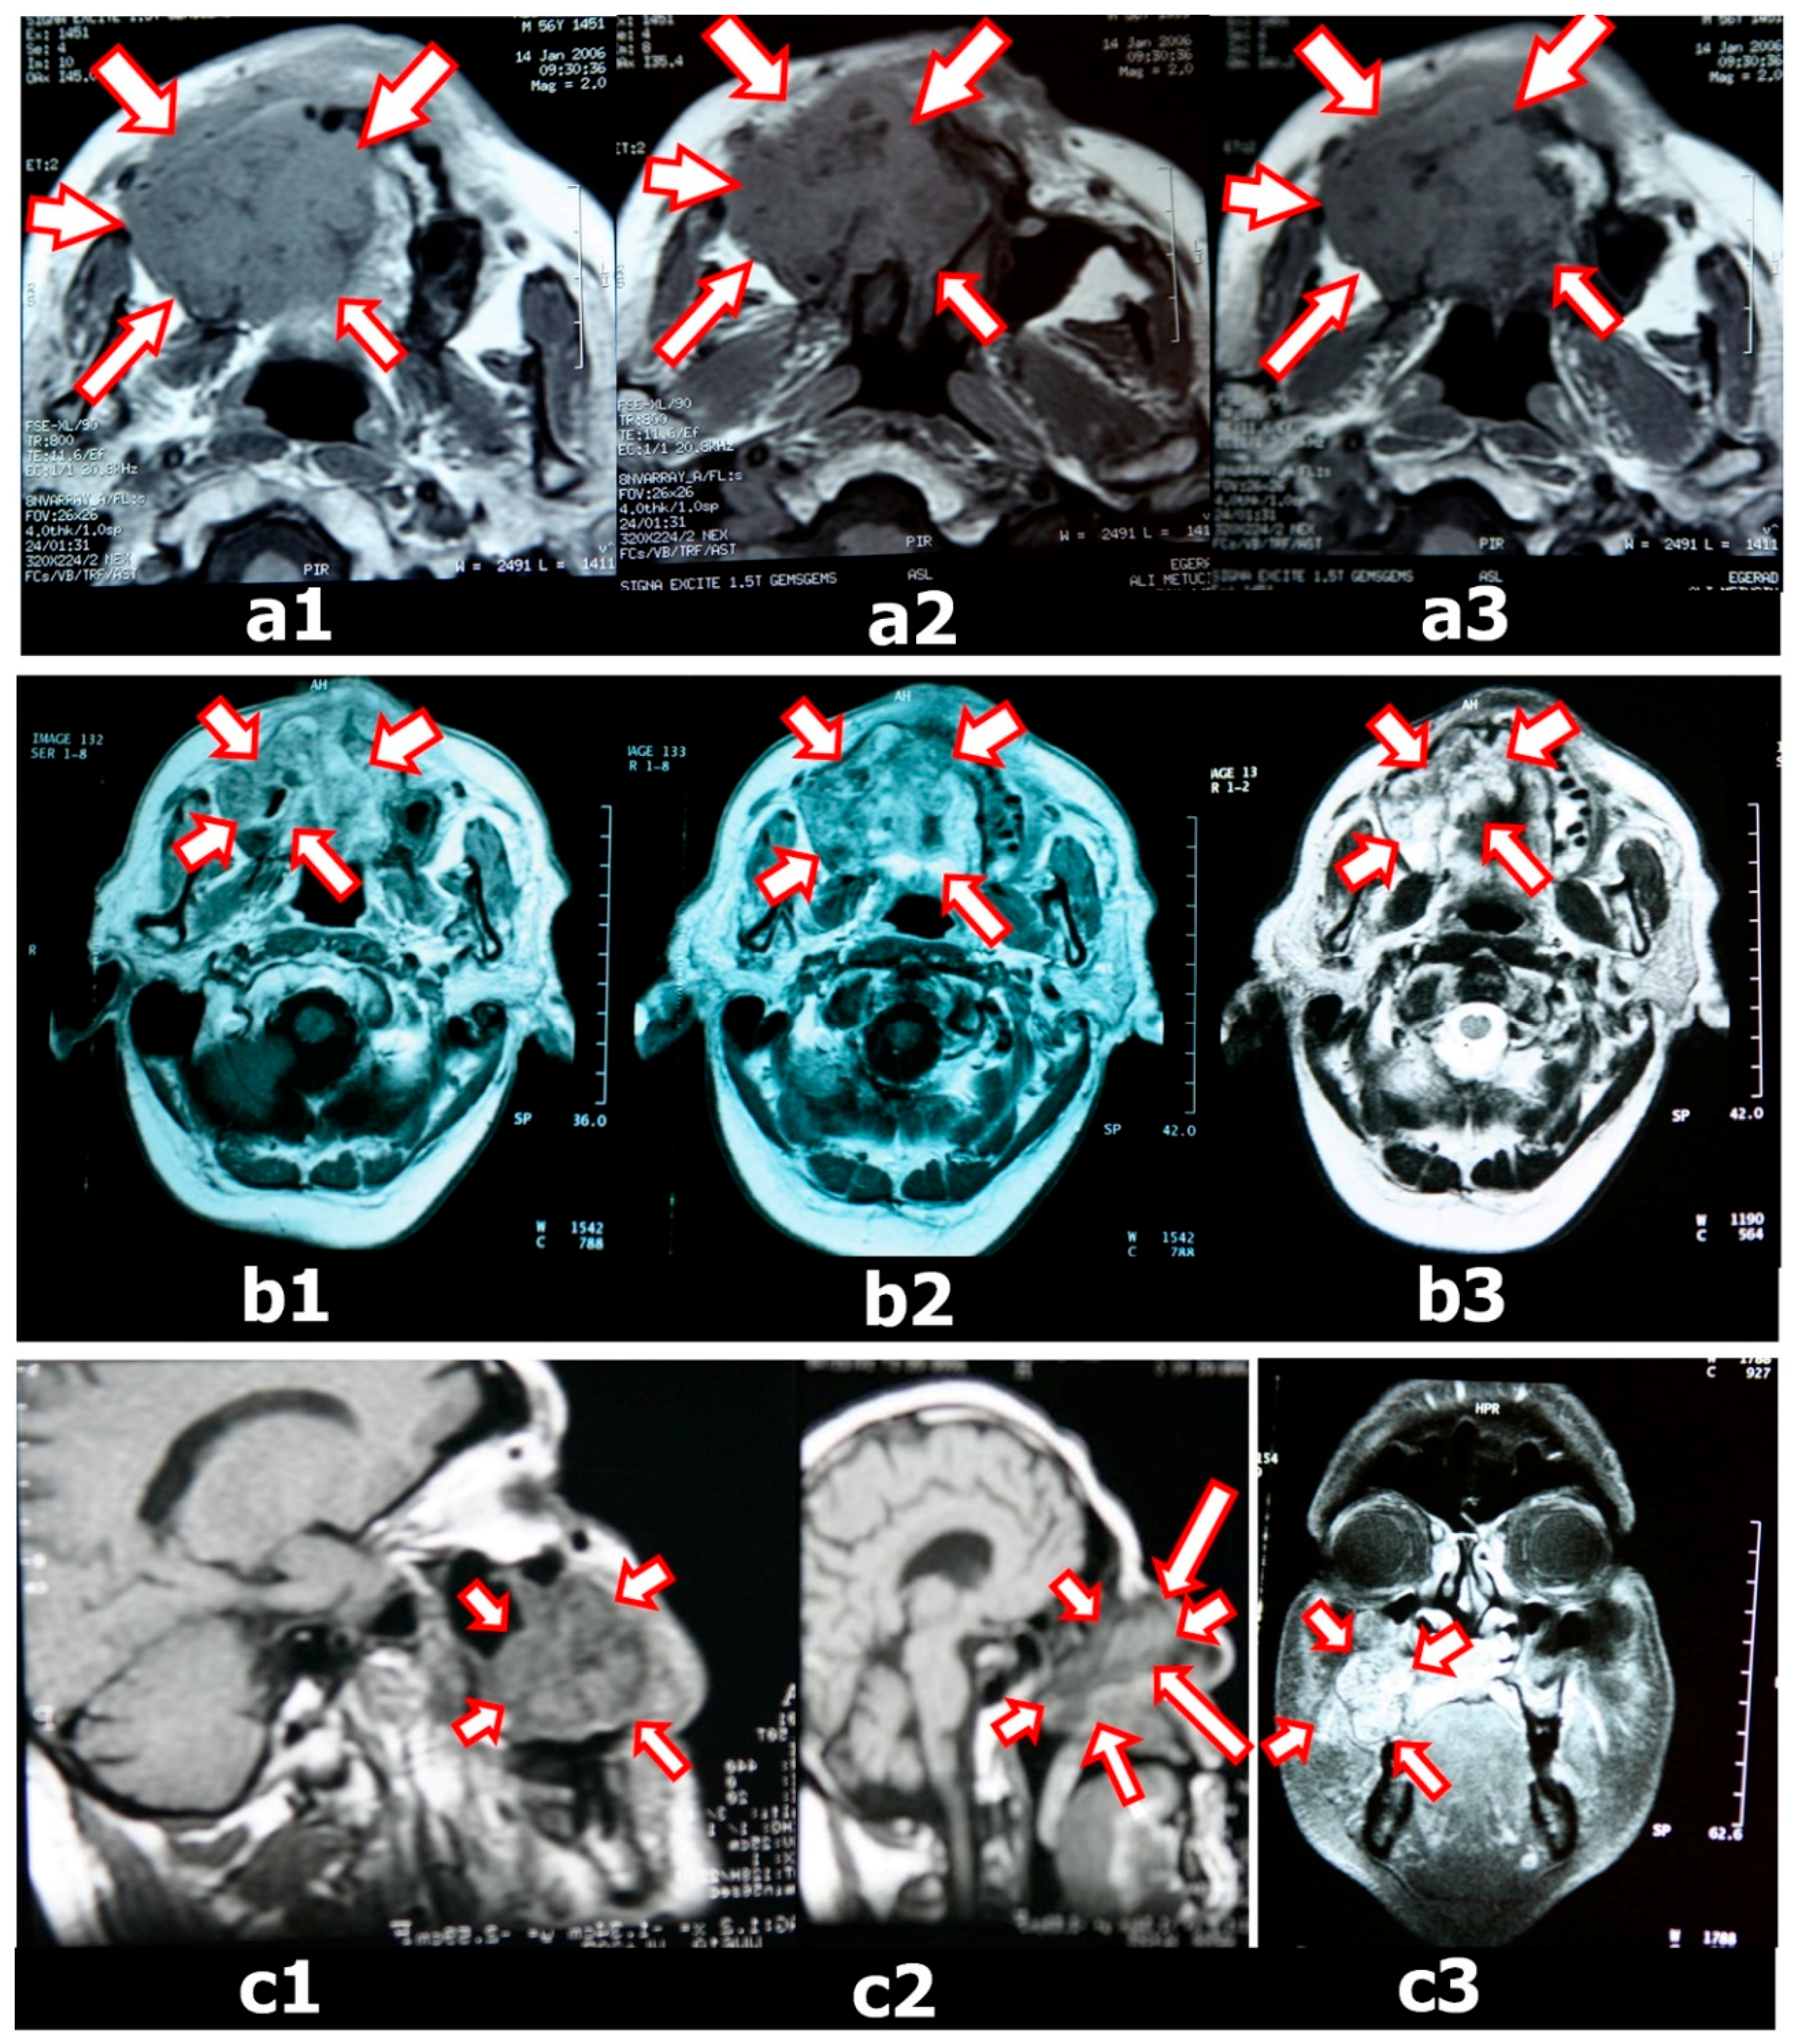

Before tumor resection, a dental impression was made using irreversible hydrocolloid impression material for fabrication of the immediate surgical obturator. Dental casts were fabricated with dental stone. The surgical limits were determined on casts with 3D tomography and MRI. The dental cast was cut from these boundaries. On the maxillary diagnostic cast, the surgical margins were plotted approximately whilst consulting with the surgical team because complete coverage of the surgical site with the obturator is crucial. Immediate obturators were prepared on these casts (Figure 3).

Figure 2. Axial and Coronal MRI weighted images showing a lesion of the maxillofacial region. (a1–3) MRI images of a palatomaxillar tumor on the horizontal plane before chemotherapy and radiotherapy (white arrows with red border); (b1–3) MRI images of the palatomaxillar tumor on the horizontal plane after chemotherapy and radiotherapy (white arrows with red border); (c) MRI images of the palatomaxillar tumor on the sagittal (c1,2) and frontal (c3) plane after chemotherapy and radiotherapy (white arrows with red border).